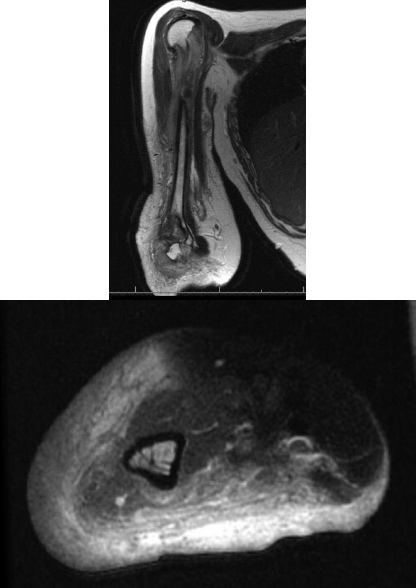

A 25-year-old woman comes to the office because of a slow-growing upper extremity mass. Physical examination also shows numerous smaller lesions and masses scattered over the patient’s body. She reports that her mother has similar lesions. MRI images are shown. Which of the following is the most likely diagnosis?

D. plexiform neurofibroma

neurofibromatosis